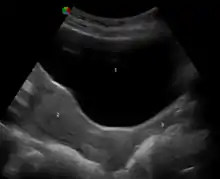

- Merz E, Bahlmann F (2004). Ultrasound in Obstetrics and Gynecology. Vol. 1. Thieme Medical Publishers. p. 129. ISBN 978-1-58890-147-7.